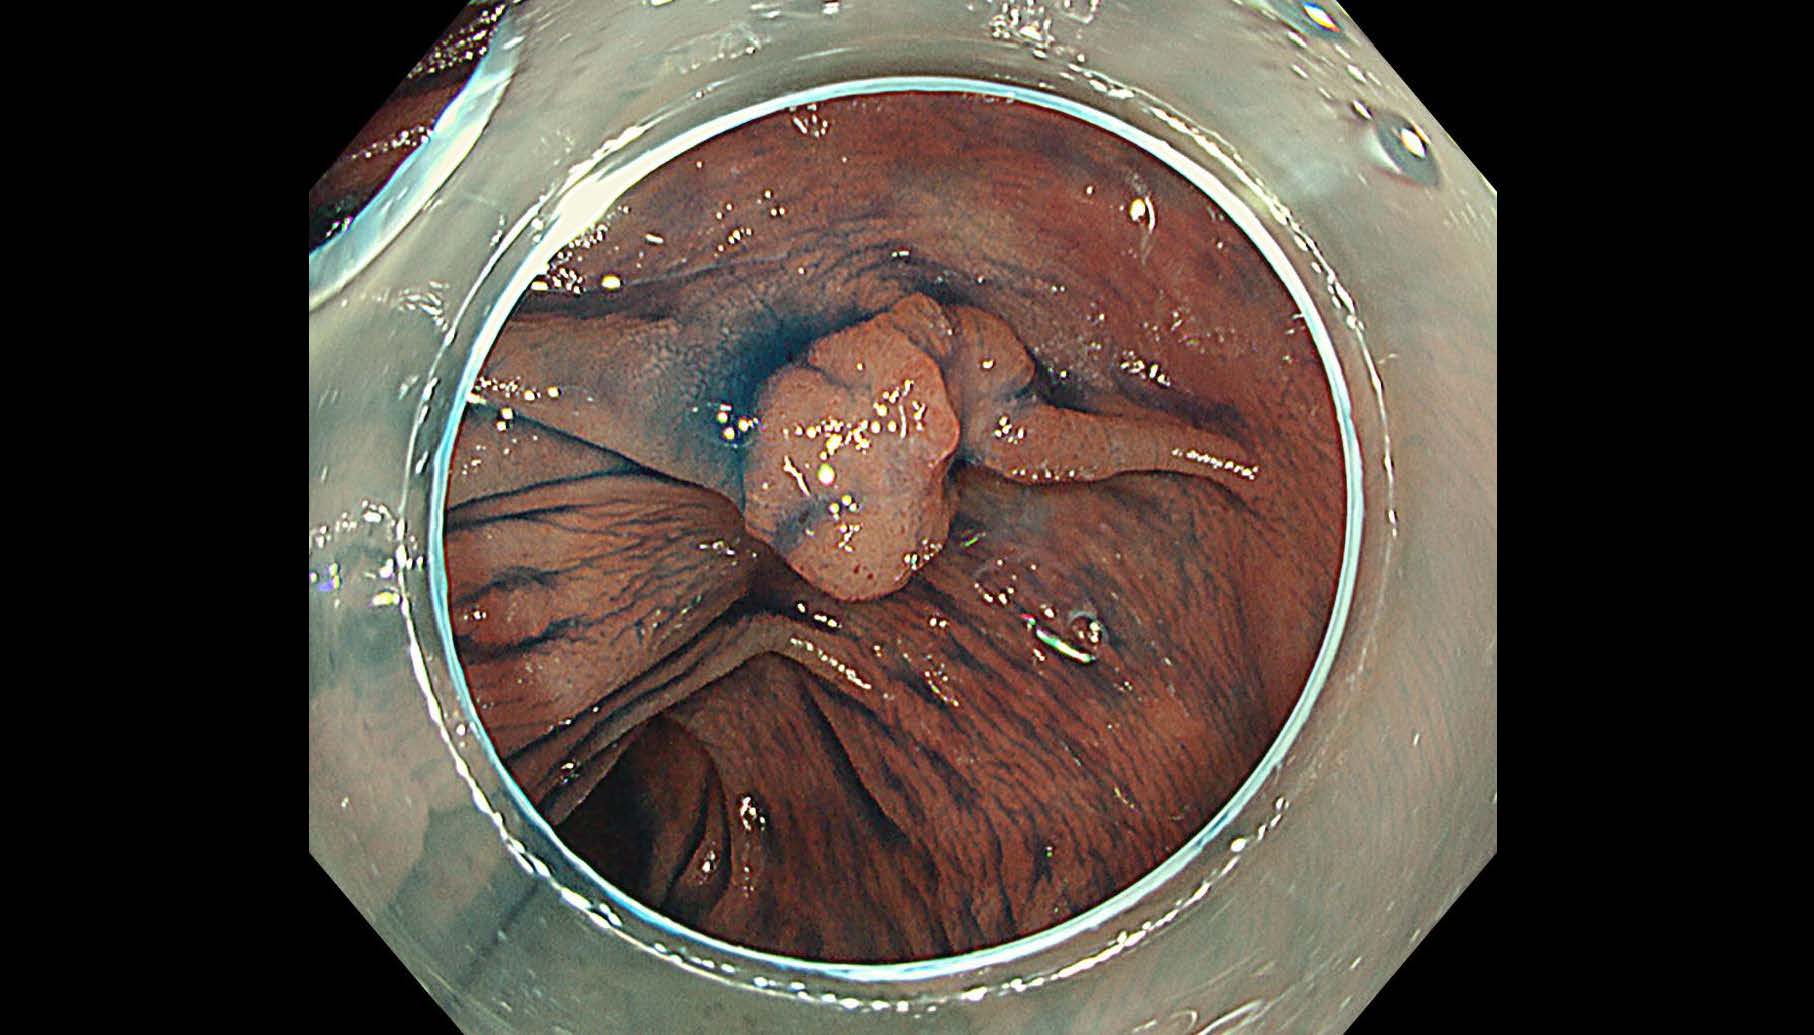

消化管Mapping~大腸~ 2025.6.11

消化管Mapping

消化管Mapping~大腸~

消化器内科

内視鏡検査・治療